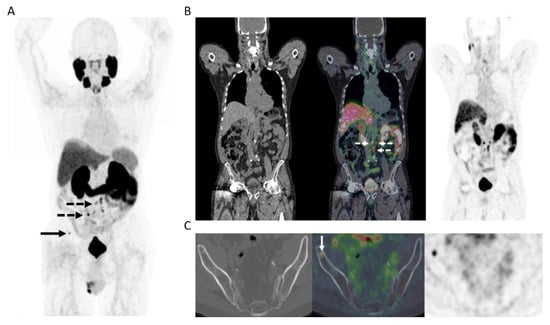

Figure 2.

65-year-old man 12 years post low-dose rate brachytherapy for cT2 ISUP Grade Group 2 adenocarcinoma of prostate. Biochemical failure (serum PSA = 19.9 ng/mL) with negative CT and bone scintigraphy. (A) MIP PET image showing extensive, multifocal abnormal radiotracer uptake in the pelvis and retroperitoneum (solid arrows), in the left supraclavicular fossa (dotted arrow), as well as a few sites in the skeleton (arrowheads). (B) Axial PET/MR image at pelvic inlet (PET–left; gadolinium-enhanced T1-weighted image–middle; fused PET/MR–right) shows an intensely PSMA avid right common iliac node (solid arrow) and a PSMA avid deposit at L5 vertebral body (arrowhead). (C) Axial PET/MR image at pelvic inlet (PET–left; gadolinium-enhanced T1-weighted image–middle; fused PET/MR–right) shows a further PSMA avid bone deposit in the scapula. After PET, the patient commenced androgen deprivation therapy.

18F-DCFPyL PET/MR was performed in 12 patients who had a clinical need for concurrent MR of the prostate, as defined above, predominantly patients post prior radiotherapy or focal tumor ablation. In all others (n = 35), 18F-DCFPyL PET/CT was obtained. Overall, PET/MR was positive in 11/12 and PET/CT was positive in 32/35 men, with overall 43 of 47 study patients (91.5%) having at least one site of residual or recurrent disease on PET. Sites of recurrence included local tumor recurrence in the prostate or prostate bed in (20/47) 42.6%, regional nodal metastases in (29/47) 61.7%, extra-regional nodal metastases in (19/47) 40.4% or skeletal metastases in (3/47) 6.4%. Local recurrence, lymph node metastases and bone metastases were histologically confirmed in 2, 3 and 2 men, respectively. Recurrence was limited to the prostate or prostate bed only in (9/47) 19.2%, oligometastatic disease in (16/47) 34% or extensive metastatic disease in (18/47) 38.3% (Figure 2). Post PET management data is summarized in Table 2.